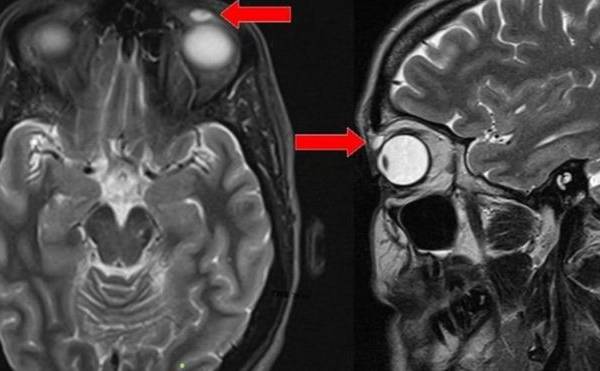

Una resonancia magnética mostró el quiste sobre el ojo de la mujer.

Los investigadores del hospital de Ninewell le realizaron una resonancia magnética, después de que el médico de cabecera de la paciente la remitiera al departamento de Oftalmología.

Las imágenes de la resonancia revelaron un quiste con forma ovoide de unos 8mm de longitud, pero no había evidencia de que hubiese algo dentro.